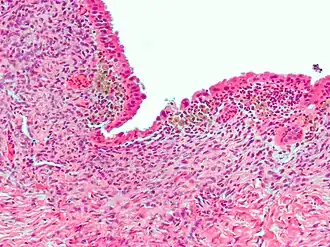

Micrografia mostrando endometriose (coloração H&E), uma causa comum de dor pélvica crônica em mulheres.

As causas comuns incluem: endometriose em mulheres, aderências intestinais, síndrome do intestino irritável e cistite intersticial.[2] A causa também pode ser uma série de condições mal compreendidas que podem representar função psiconeuromuscular anormal.